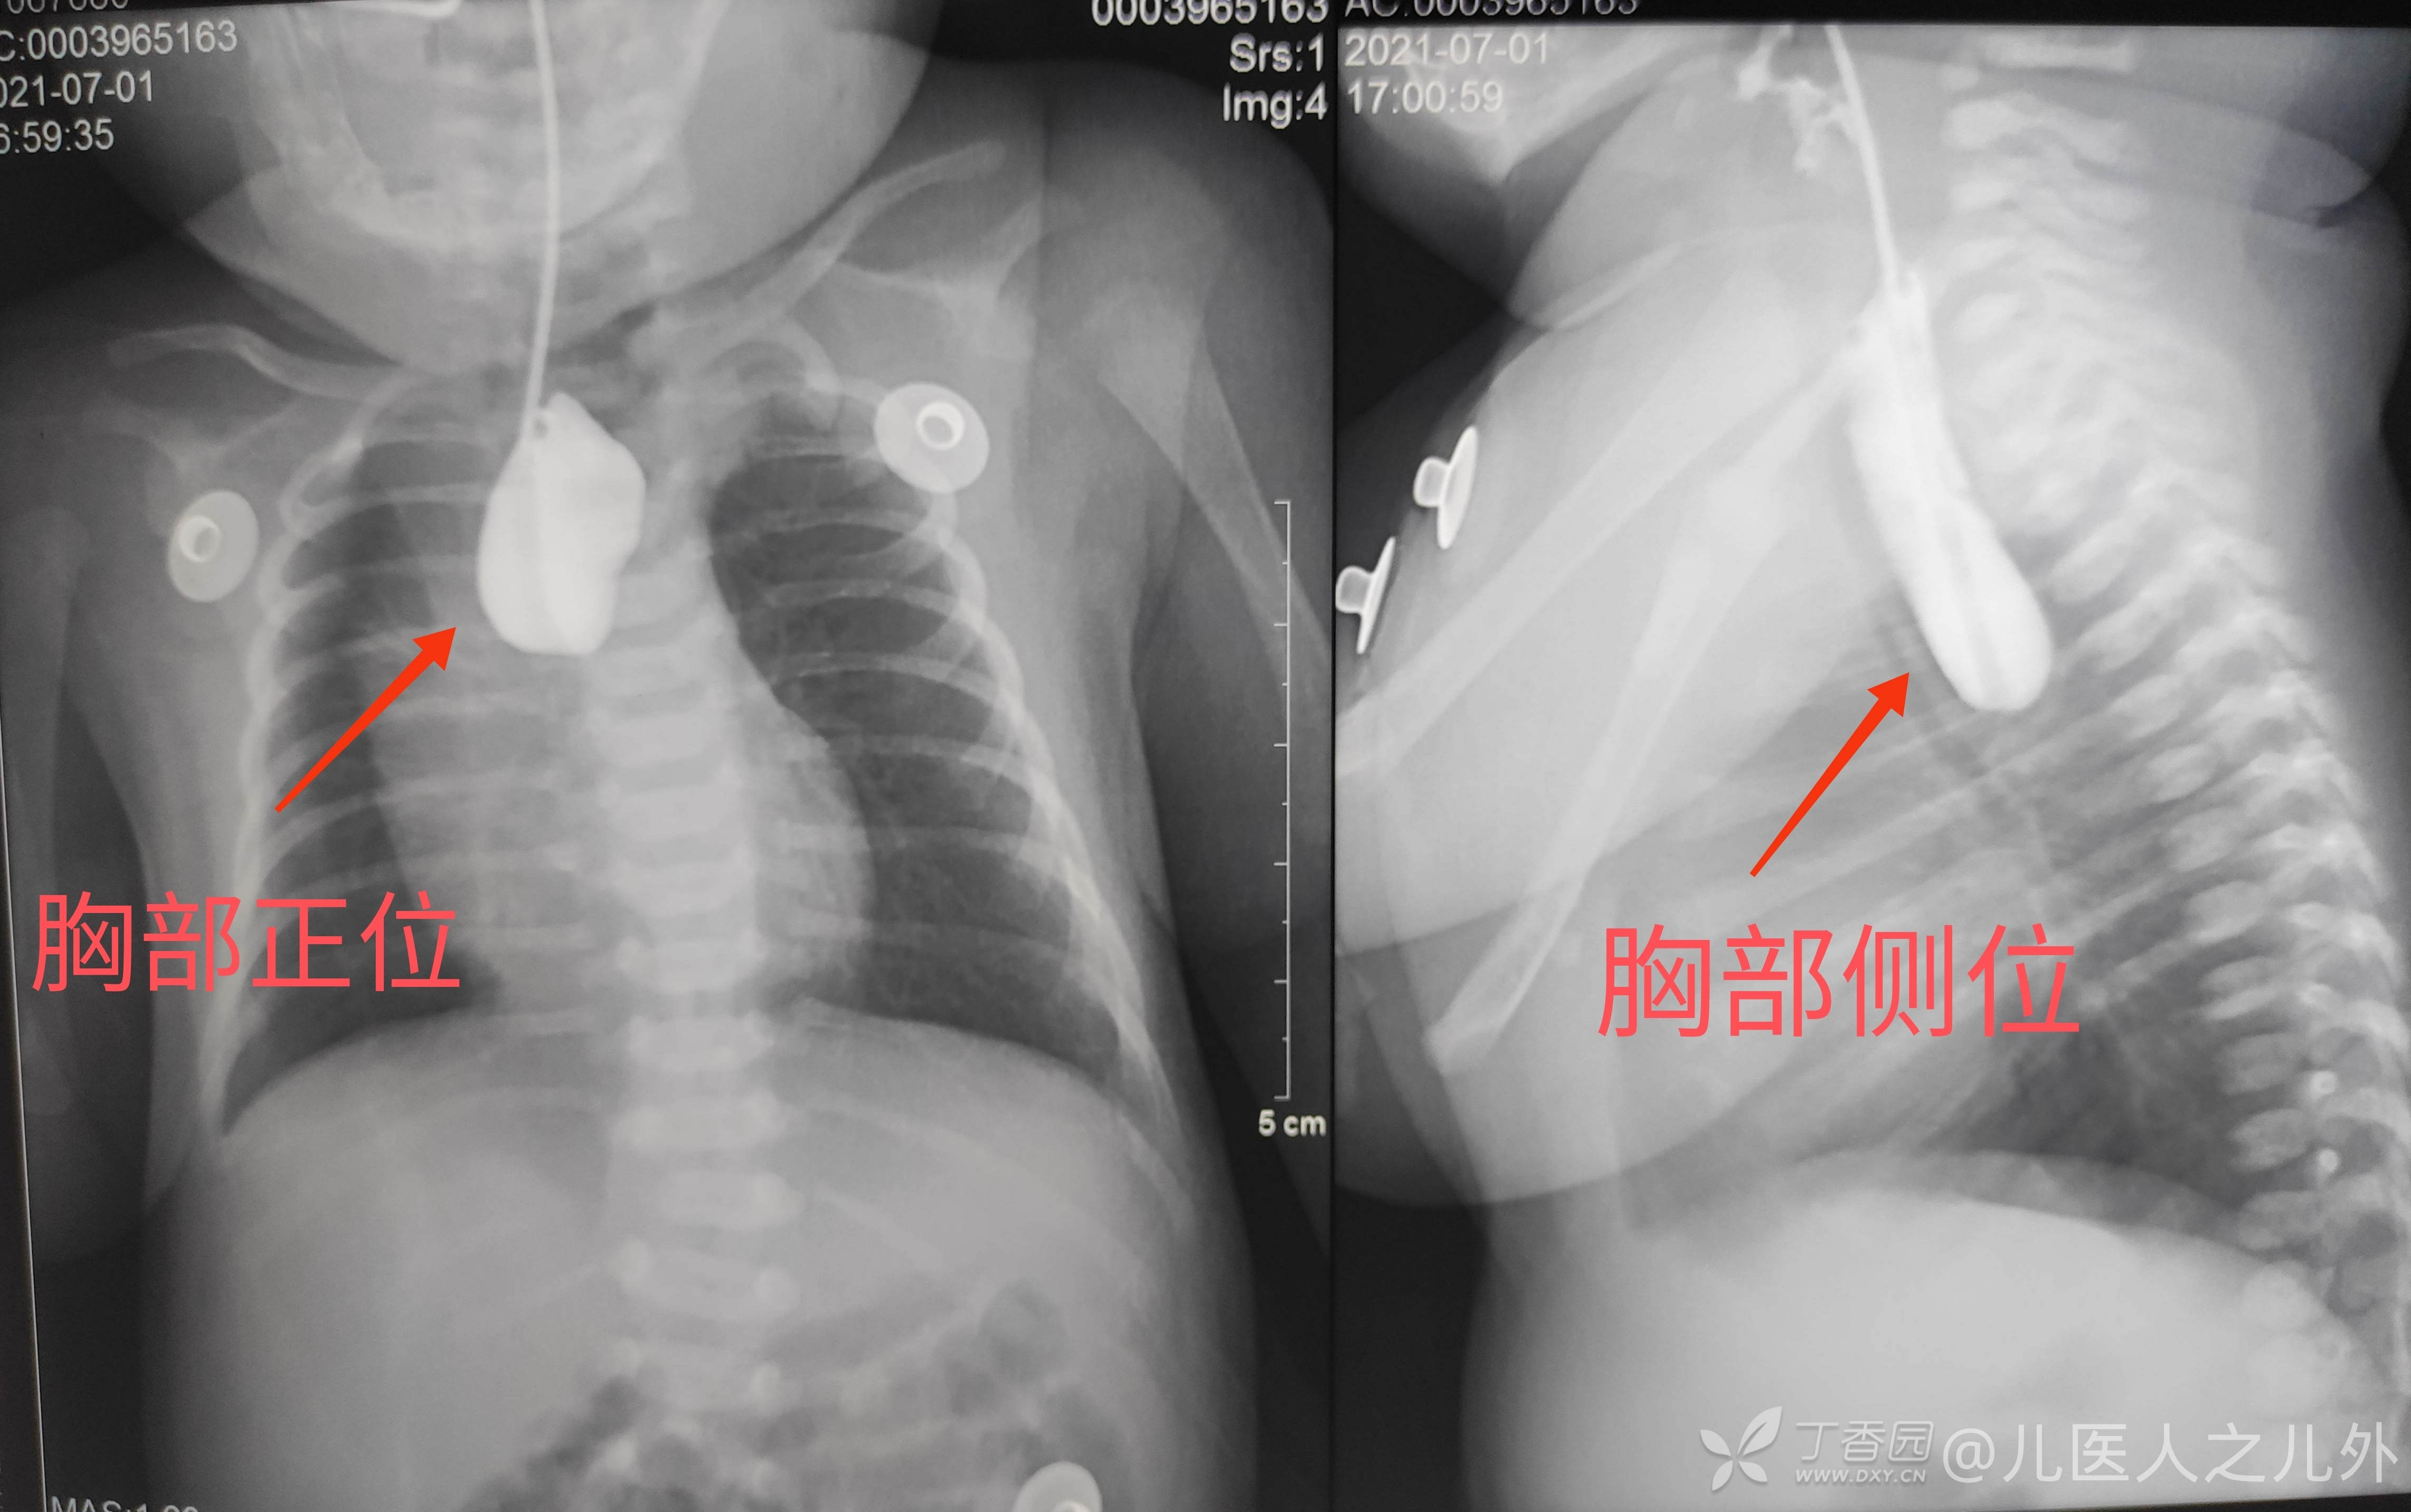

食道造影结果如下图所示,

胸部正侧位可以明显看到食管的上盲端。乘着造影剂没有完全排出肠道,做胸部CT如下图所示,